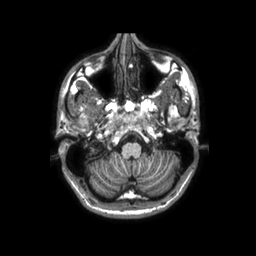

Encefalo: immagini assiali pesate in T1

Selezione di immagini pesate T1 ad alta risoluzione spaziale (dimensione del voxel 1x1x1 mm)